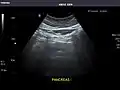

- Pancreas

Pancreas: Visualized portions unremarkable.